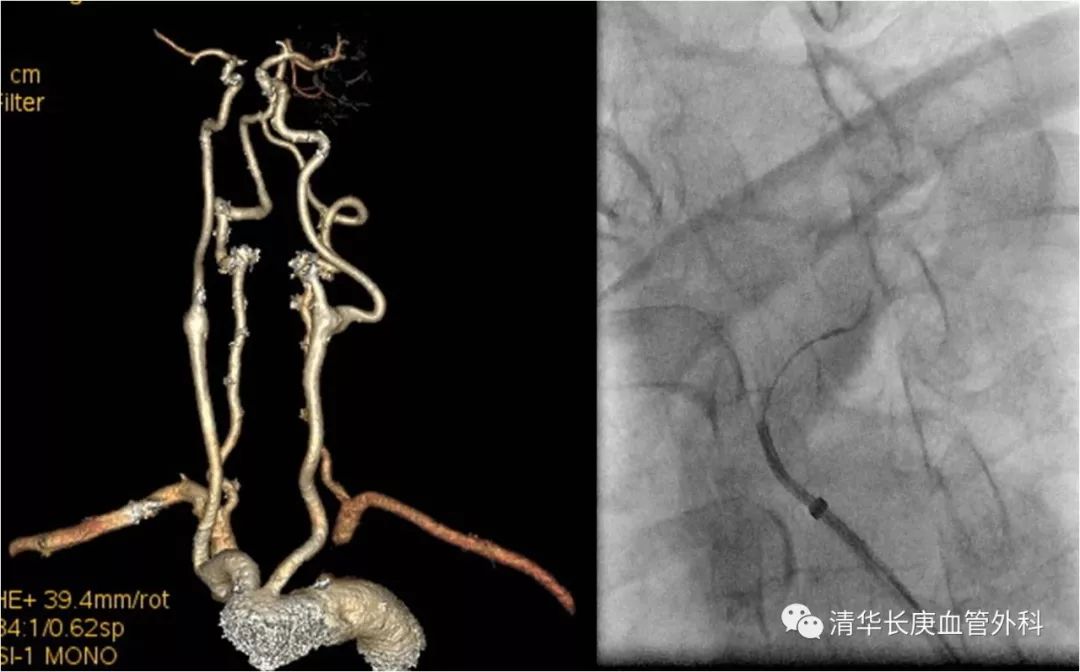

实战手术最具魅力,吴巍巍主任主刀演示胸腹主动脉瘤近端“原位开窗”、远端“改序”释放腔内修复术,将一例以往开胸开腹体外循环都难以修复的主动脉瘤“大”手术巧妙地转化为仅需要三个穿刺点的微创“小”手术,原位开窗精准利落,改序释放巧妙稳固,赢得了在场学员的称赞。

赵克强副主任医师,以典型病例录播形式,向学员们分享了弓上动脉病变的治疗,包括锁骨下动脉闭塞、复杂弓型颈动脉支架的入路建立、多发病变、串联病变的治疗策略,以及弓上病变围术期管理、术中技巧、常见并发症及预防措施;学员们积极踊跃、畅所欲言、交流心得,对弓上病变的诊治有了进一步的认识、体会。

锁骨下动脉闭塞,长鞘+椎管+CXI+V18同轴系统通过病变

双导丝技术

不友好弓型的入路建立